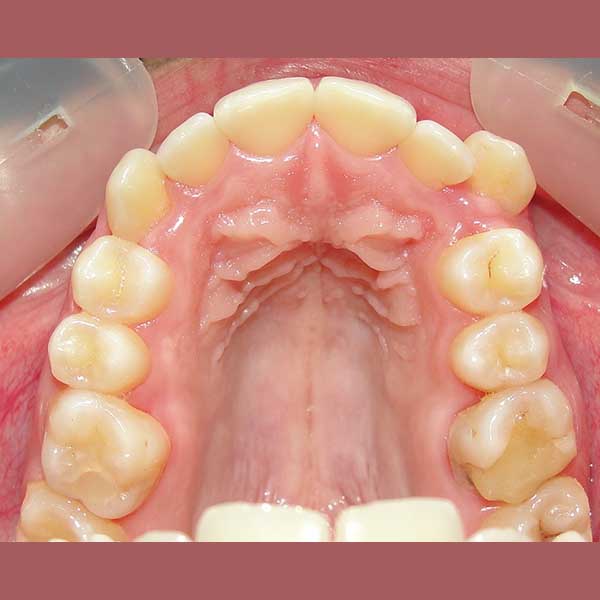

لحسن الحظ، وبعد دراسة الحالة، أكد الدكتور خالد الكاتب أن العلاج ممكن دون الحاجة للقلع. تم اختيار تقويم الدايمون (ذاتي الربط)، لما له من قدرة ممتازة على المساعدة في توسيع الفكين وتحريك الأسنان بفعالية لتوفير المسافة المطلوبة. سمحت هذه التقنية بحل الازدحام وإنزال الناب المرتفع إلى مكانه الصحيح.